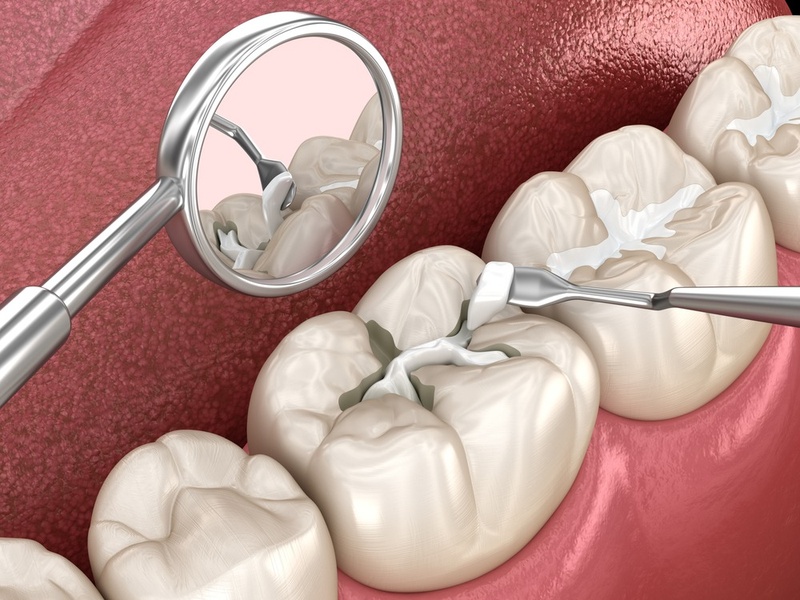

- Trám răng: Phù hợp cho vết nứt nhỏ, không ảnh hưởng đến cấu trúc răng. Phương pháp này sử dụng vật liệu composite có màu sắc tương đồng với màu răng thật để lấp đầy vết nứt. Ưu điểm là quy trình nhanh chóng, đơn giản và chi phí tương đối thấp. Tuy nhiên, độ bền không cao và không hiệu quả cho vết nứt lớn hoặc kéo dài xuống chân răng.